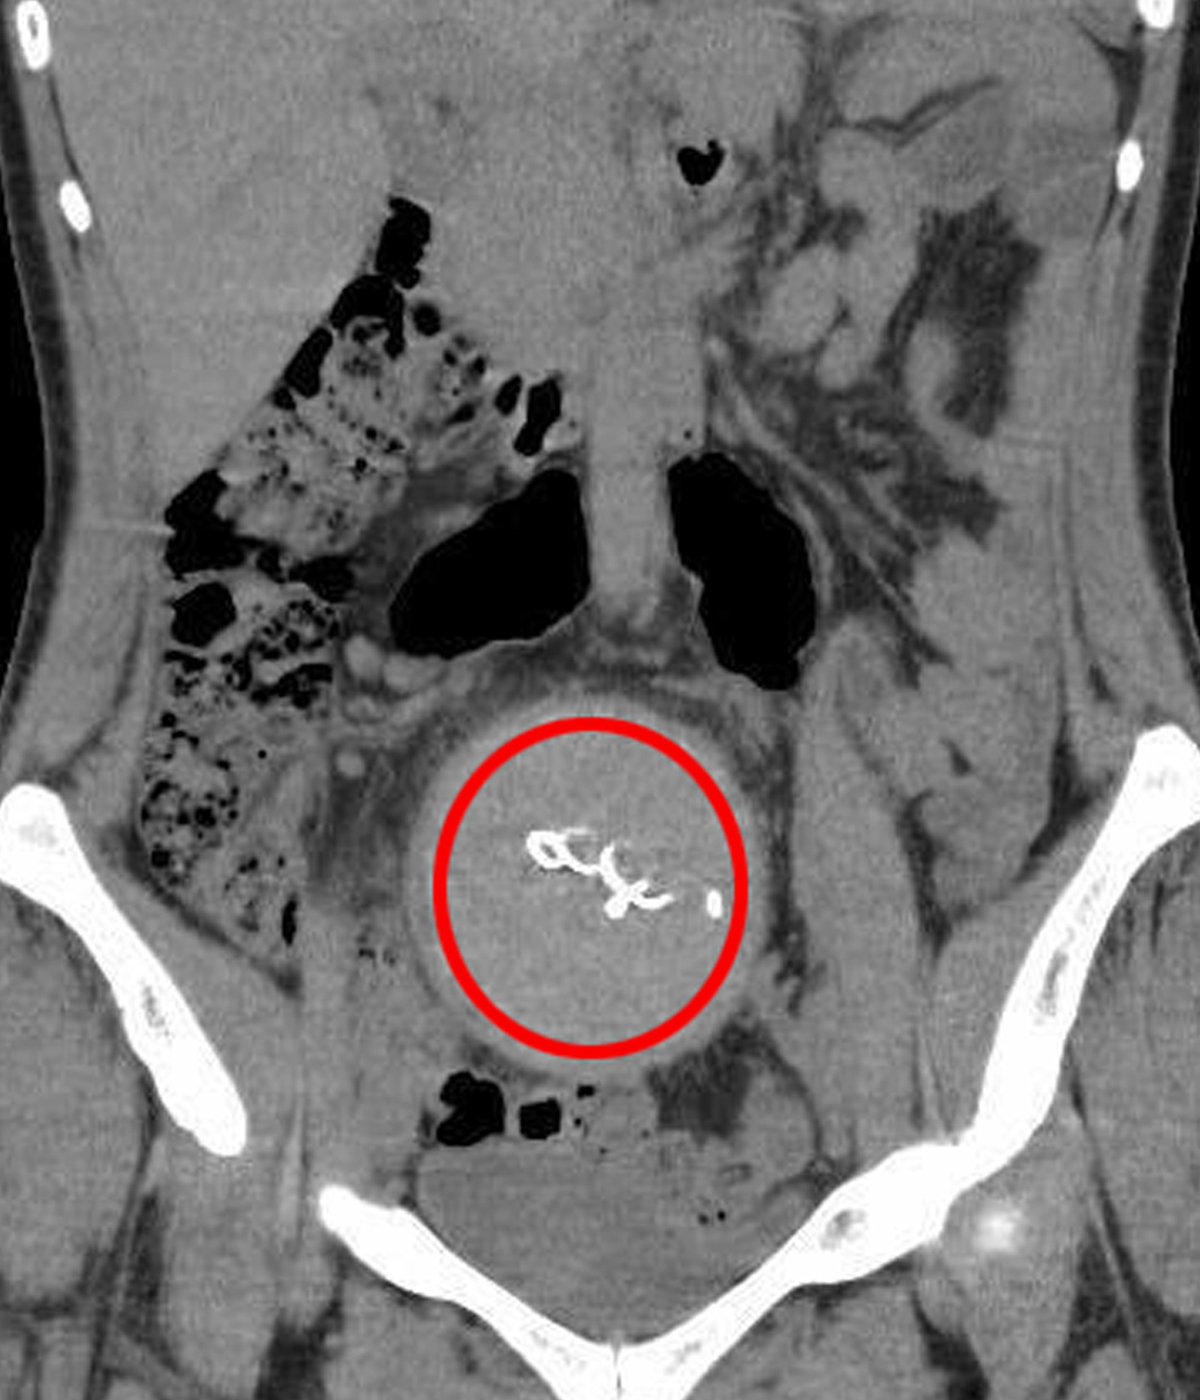

Burada yapılan kontrolde doktor acil tomografi çektirmesini istedi. Çekilen tomografide Y.S.’nin vücudunda doğum sonrası unutulan sargı bezi görüldü. Büyük şok yaşayan Y.S., 2 yıldır yaşadığı ağrılara ihmalin sebep olduğunu öğrendi. Y.S.'nin karnında unutulan yaklaşık 30 santimetre uzunluğundaki gazlı bez ameliyatla çıkarıldı. Y.S., hastane ve doktor hakkında hukuki süreci başlatması için avukatı Hasret Baş’a başvurdu.